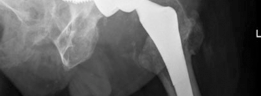

Reconstruction techniques : A hemispherical socket was placed; however, in the presence of posterior wall deficiency, a buttress augment was utilized to support the socket. The cup was fixed with multiple screws, and demineralized bone matrix was placed behind the acetabulum. The augment and the acetabular components were adjoined with the use of cement (Figs. 19.25 and 19.26).

Challenges and solutions: Posterior wall deficiency was resolved with tantalum trabecular metal buttress augmentation of the hemispherical cup.

Unanticipated problems and solution: Deficient bone stock led to challenges in securing buttress augment. This was resolved with application of cement to adjoin the cup and the augment. The cup was also secured with multiple points of fixation.

(Figs. 19.25 and 19.26)